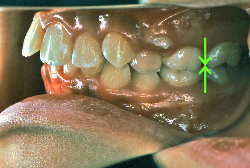

「ものがうまく噛めない」という主訴で来院したケースです。診断の結果、「骨格性反対咬合に伴う咬合不良+軽度叢生」と判明しました。原因としては特に下顎の左側が過成長したため、骨格性反対咬合になり、特に左側での噛み合わせが非常に悪くなっていると診断しました。初診時の写真を見ると、上下の正中線の大きなズレ、左側の噛み合わせの不良がはっきり分かります(黄色の矢印と緑の矢印は一致しているのが正しい状態です)。

そもそも、このような状態となっているのは骨の大きさに問題があるため生じていますので、場合によっては、「外科矯正」によって下顎の骨を外科的に縮めることで修正します。患者様が外科矯正をご希望されない場合は、従来ですと上下左右の小臼歯抜歯を行い矯正するのが普通です。

今回の患者様の場合は、「外科」も「小臼歯抜歯」も拒否されましたので、歯科矯正用アンカースクリュー(以下 アンカースクリュー)を用いて、下顎の歯列全体を後方に下げるという方法を取りました。

治療中の写真で、アンカースクリューより歯を後ろへ牽引しているのがお分かりいただけるかと思います。牽引を1年ほど続け、途中補助的に上下にゴムをかける(これを顎間ゴムと言います)手法なども追加し、全体で21ヶ月で治療を終えることが出来ました。

結局歯の本数を減らすことなく、すべてご自分の歯を残して、正しい配列と噛み合わせにすることができました。凸凹があまりひどくないため、簡単そうに見えると思いますが、このケースの初診の状態を見ると、熟練の矯正歯科医でも悩みのつきないケースです。まして、外科も出来ない、抜歯もイヤ、と言うことになると、従来の方法では治療不可能と考えられるのですが、アンカースクリューを使うことで最近は不可能が可能となってきました。